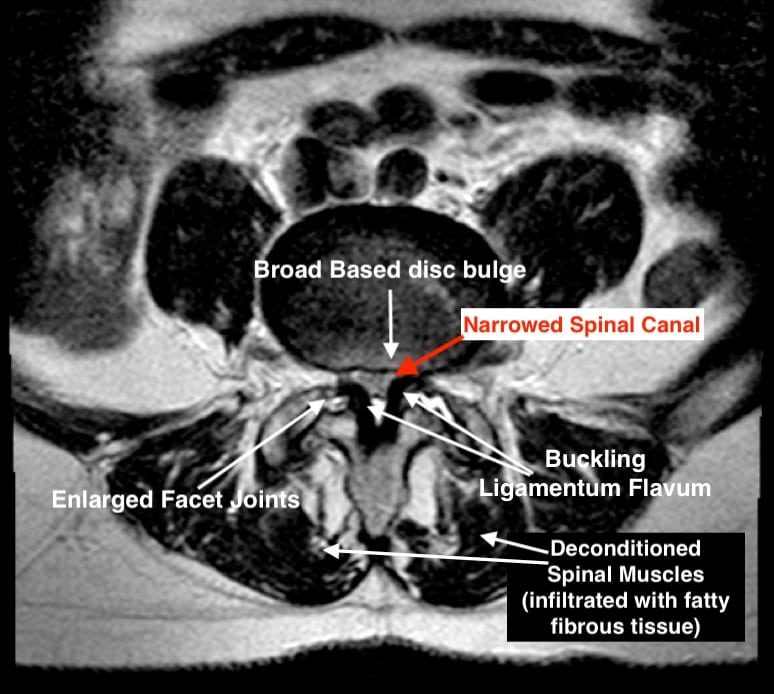

Computerised, Intervertebral Disc Decompression (IDD) Therapy is an advanced, non-invasive, spinal decompression therapy treatment and ALTERNATIVE TO INJECTIONS & SURGERY for spinal disc problems - Contact us via email TODAY ([email protected]) for your FREE copy of our IDD Therapy info pack.

We are also a specialist centre for Spinal Decompression Therapy (IDD Therapy). IDD is one of the fasted growing and

most effective non-surgical treatments for chronic back pain, sciatica and neck pain due to bulging, herniation, slipped or degenerative discs (e.g. L4/5, L5S1) in the spine.

Yes. IDD Therapy is a safe alternative to spinal surgery. It's available at our Hornchurch clinic and helps relieve disc bulges, sciatica and chronic lower back pain. settings.

Do I need an MRI Scan to Receive IDD Therapy

Yes. To receive IDD Therapy need to have had an MRI scan (of your neck or lower back), this is so we can assess your suitablity and so we know which disc to target. Learn more about IDD Therapy - click here.

Can you refer me for an MRI scan

Yes! We work closely with several MRI centres, we have "preferred status" with these centres (such as InHealth Hornchurch) and can organise specialised spinal sequences, and MRI reports from specified radiologists from the Royal National Orthopaedic Hospital (UK's leading radiologists), at no extra cost. Such sequences and reports are usually obtainable elsewhere (including on the NHS). The average cost of spinal MRI' scans we organise is £350. Furthermore, our Osteopaths have received specialist training in spinal MRI interpretation and making MRI referrals.